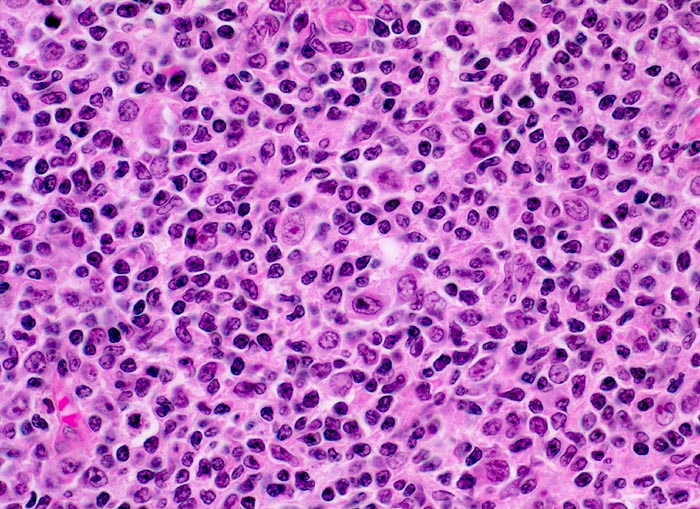

Follikuläres B-Zell Non-Hodgkin-Lymphom: neoplastisches Keimzentrum

Neoplastisches auffallend monotones Follikelzentrum bestehend aus kleinen lymphoiden Zellen mit eckigen Kernen, kaum erkennbaren Nukleolen und wenig Zytoplasma (Zentrozyten). Daneben finden sich grössere follikulär dendritische Zellen mit blassem Kernchromatin, zentralen Nukleolen und hellem Zytoplasma mit hier kaum sichtbaren fein ausgezogenen Ausläufern.

Die Keimzentren sind immunhistochemisch positiv für bcl-2.